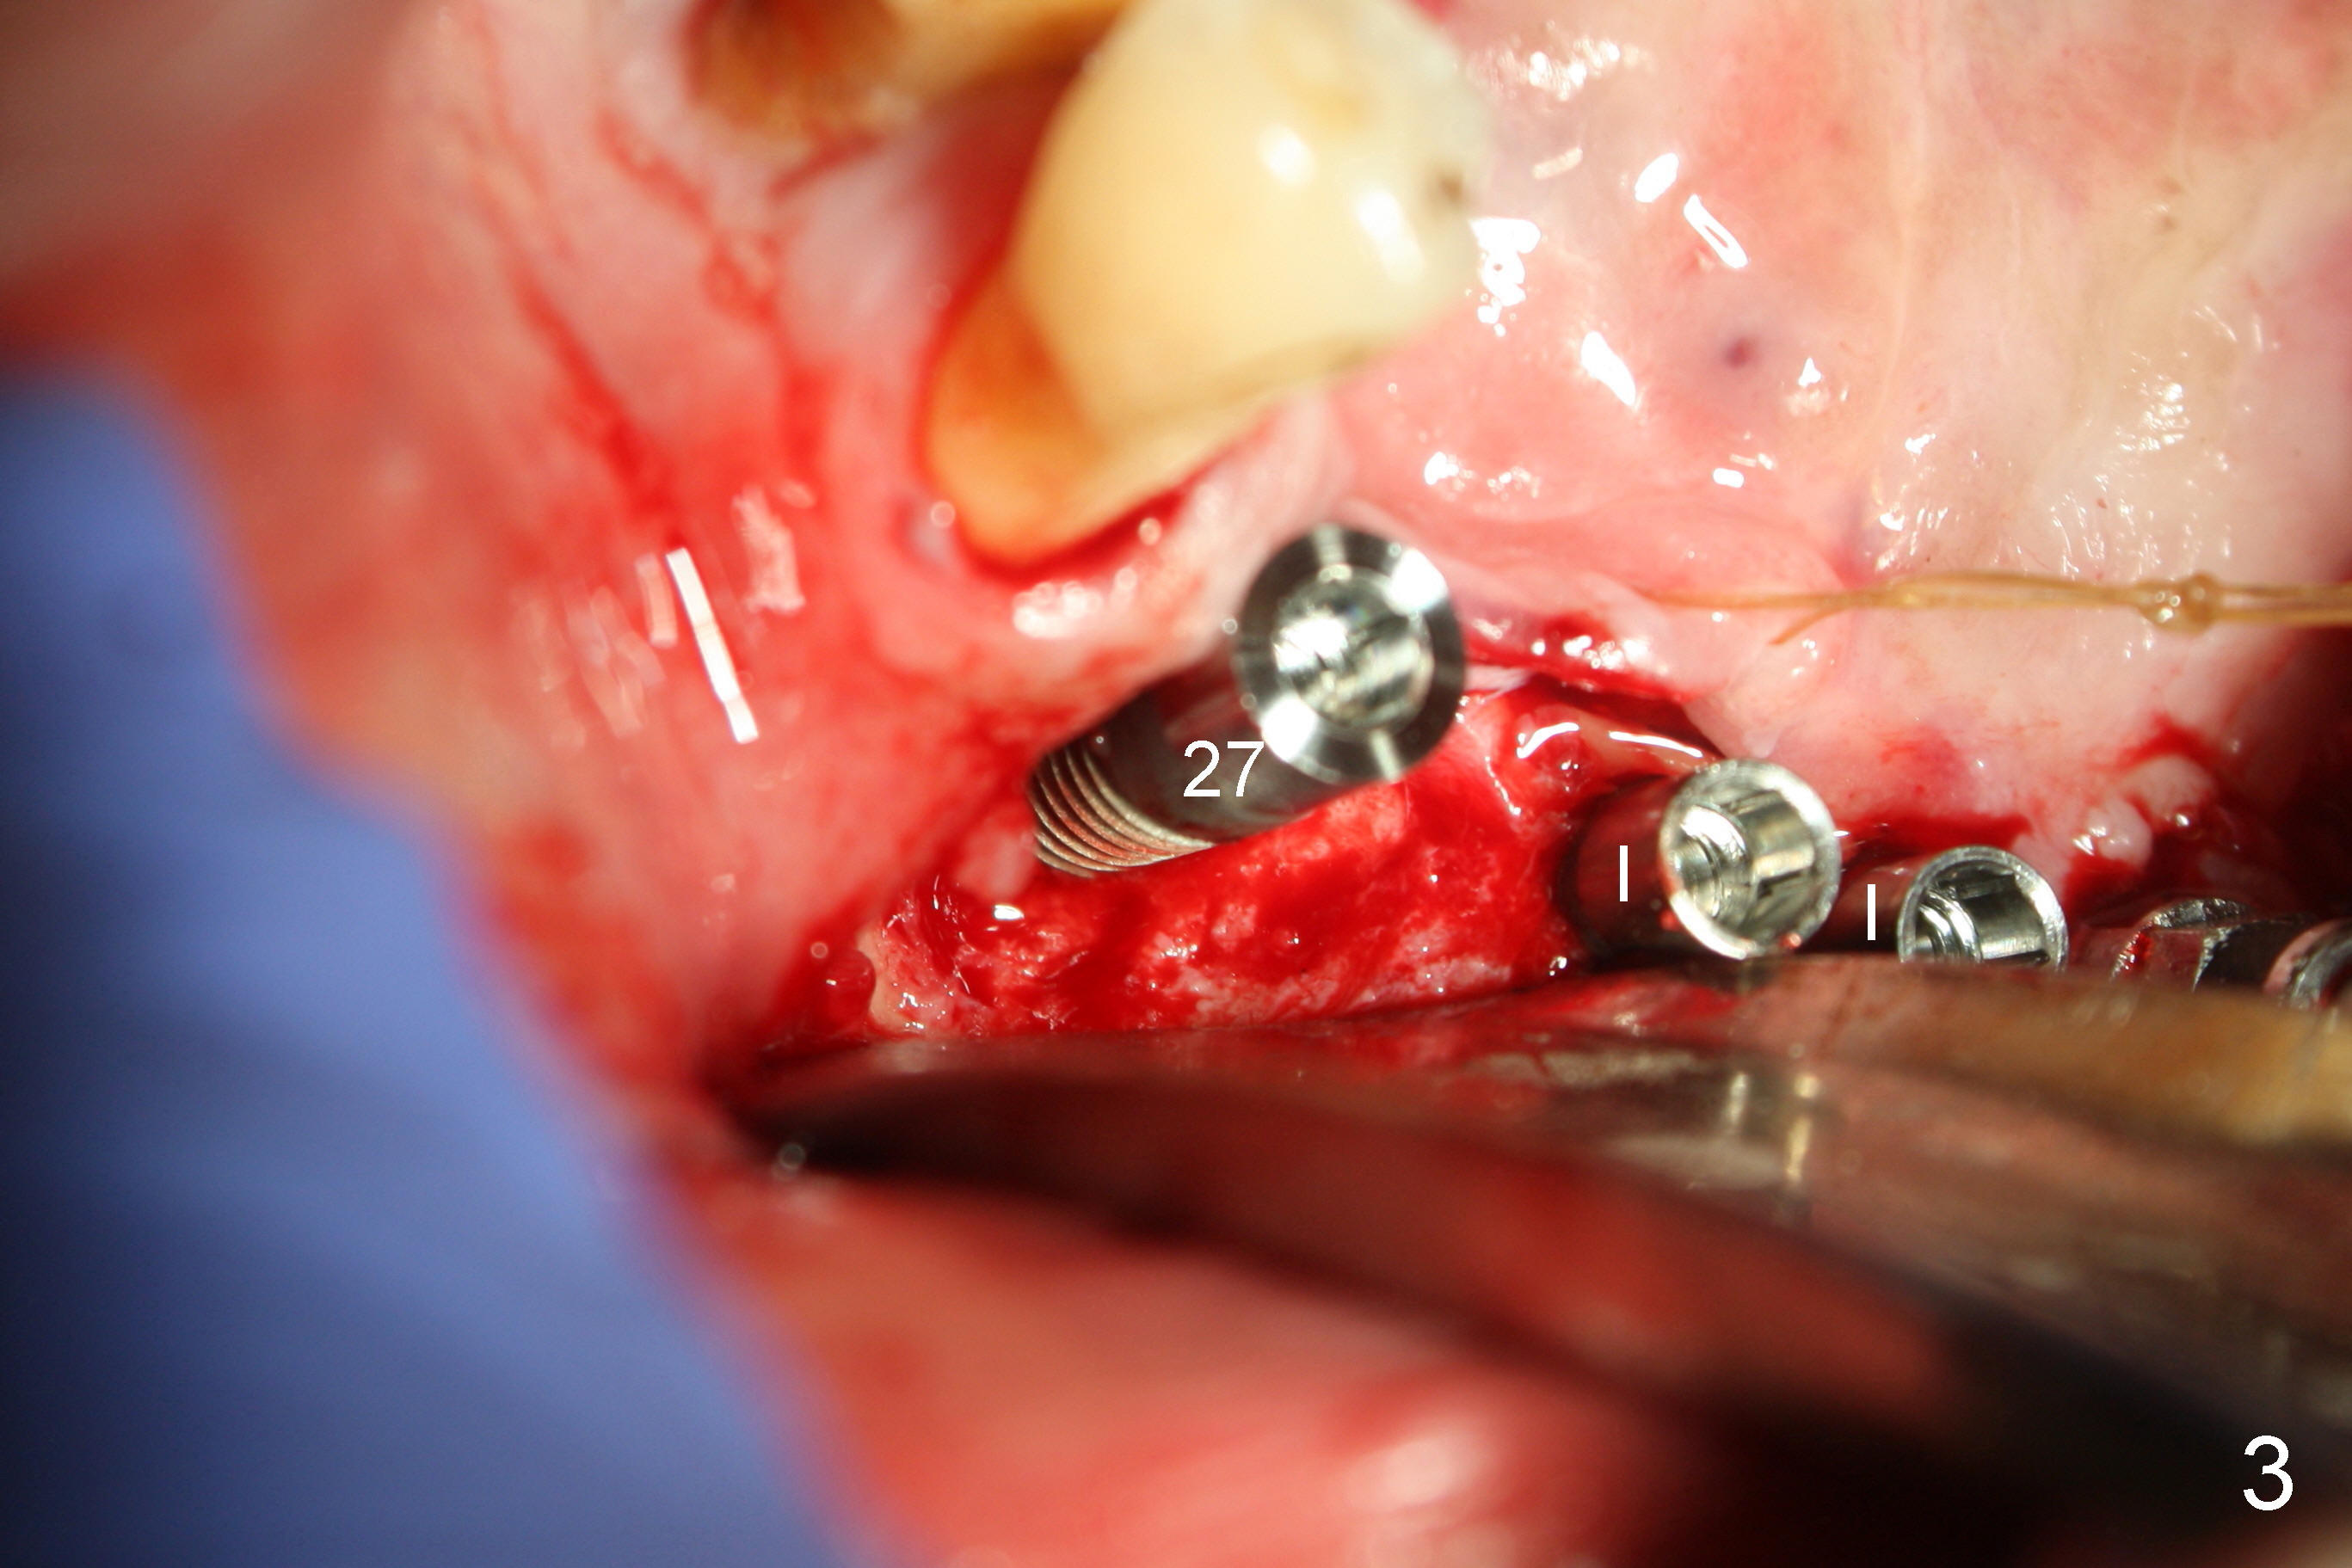

Treatment plan of the 1st surgery consists of extraction of #20 and 21/immediate implants (Fig.1 x), and placement of 4 implants between #22 and 27. Osteotomy at the extraction sites without incision (close surgery) turns out to be difficult; it appears to encroach the inferior alveolar nerve and mental loop. The sockets are subsequently bone grafted (Fig.2 *: mixture of autogenous bone and allograft). Incision is the made in the incisor edentulous region for placement of 3.5x17 mm implants (Fig.3 I).

Osteotomy is initiated through the gingiva of the healing sockets at the sites of #22 and 27 (Fig.1) with difficulty (close surgery). The incisor crest incision is extended distal to the canine areas; an accessory oblique incision is supplemented to facilitate implantation (#22: 5x14 mm; #27: 4.5x17 mm) and expose the buccal defects (Fig.3,4, open surgery). The defects are grafted (Fig.5) and covered by collagen membrane (Fig.6). The incisions are closed and abutments are placed for immediate provisional (Fig.7).